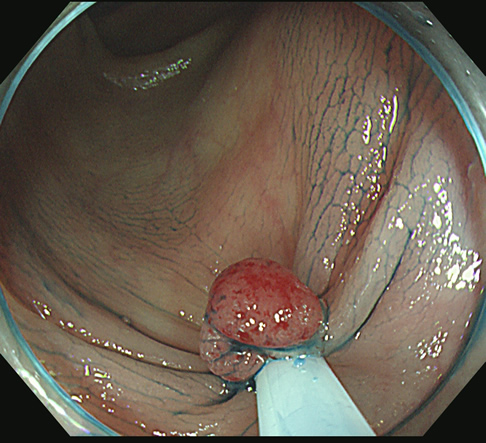

カンシで右上方向を追加切除します

細胞を1個も残さないことが肝要です。

1個でも残れば再発し、やがて癌化します!

「広めに取り過ぎた」位が安全であり、望ましいと考えています。